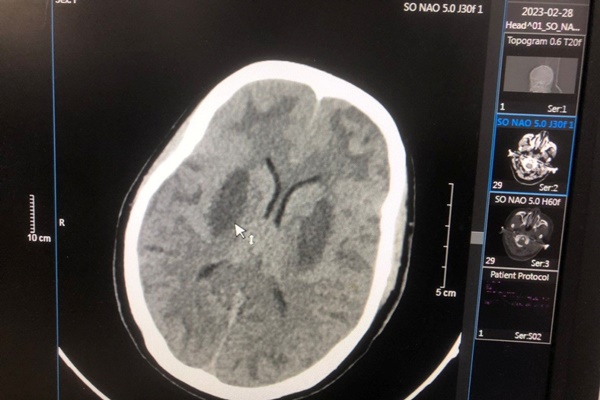

Sau đó, anh được chuyển tới Trung tâm Chống độc, Bệnh viện Bạch Mai, trong tình trạng hôn mê, tụt huyết áp, nhiễm toan chuyển hóa nặng, tổn thương não nặng hai bên, nồng độ methanol trong máu là 125 mg/dL, không có ethanol. Bệnh nhân đã được cấp cứu điều trị hồi sức giải độc lọc máu, hiện tri giác có cải thiện nhưng não vẫn tổn thương và phù não nhiều, tổn thương mắt.

Hình ảnh tổn thương não của bệnh nhân T.V.N. Ảnh: BSCC